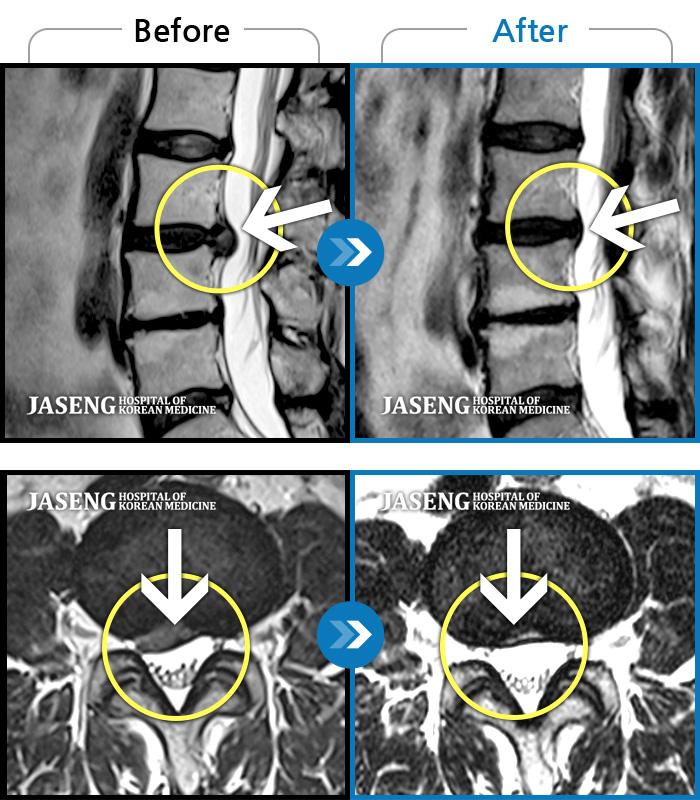

[뱸] 19.11.28~25.05.06

ȯںп Ǹ ǿ ԿǾ, ο ġ ۿ Ƿ ġḦ Ͻñ ٶϴ.